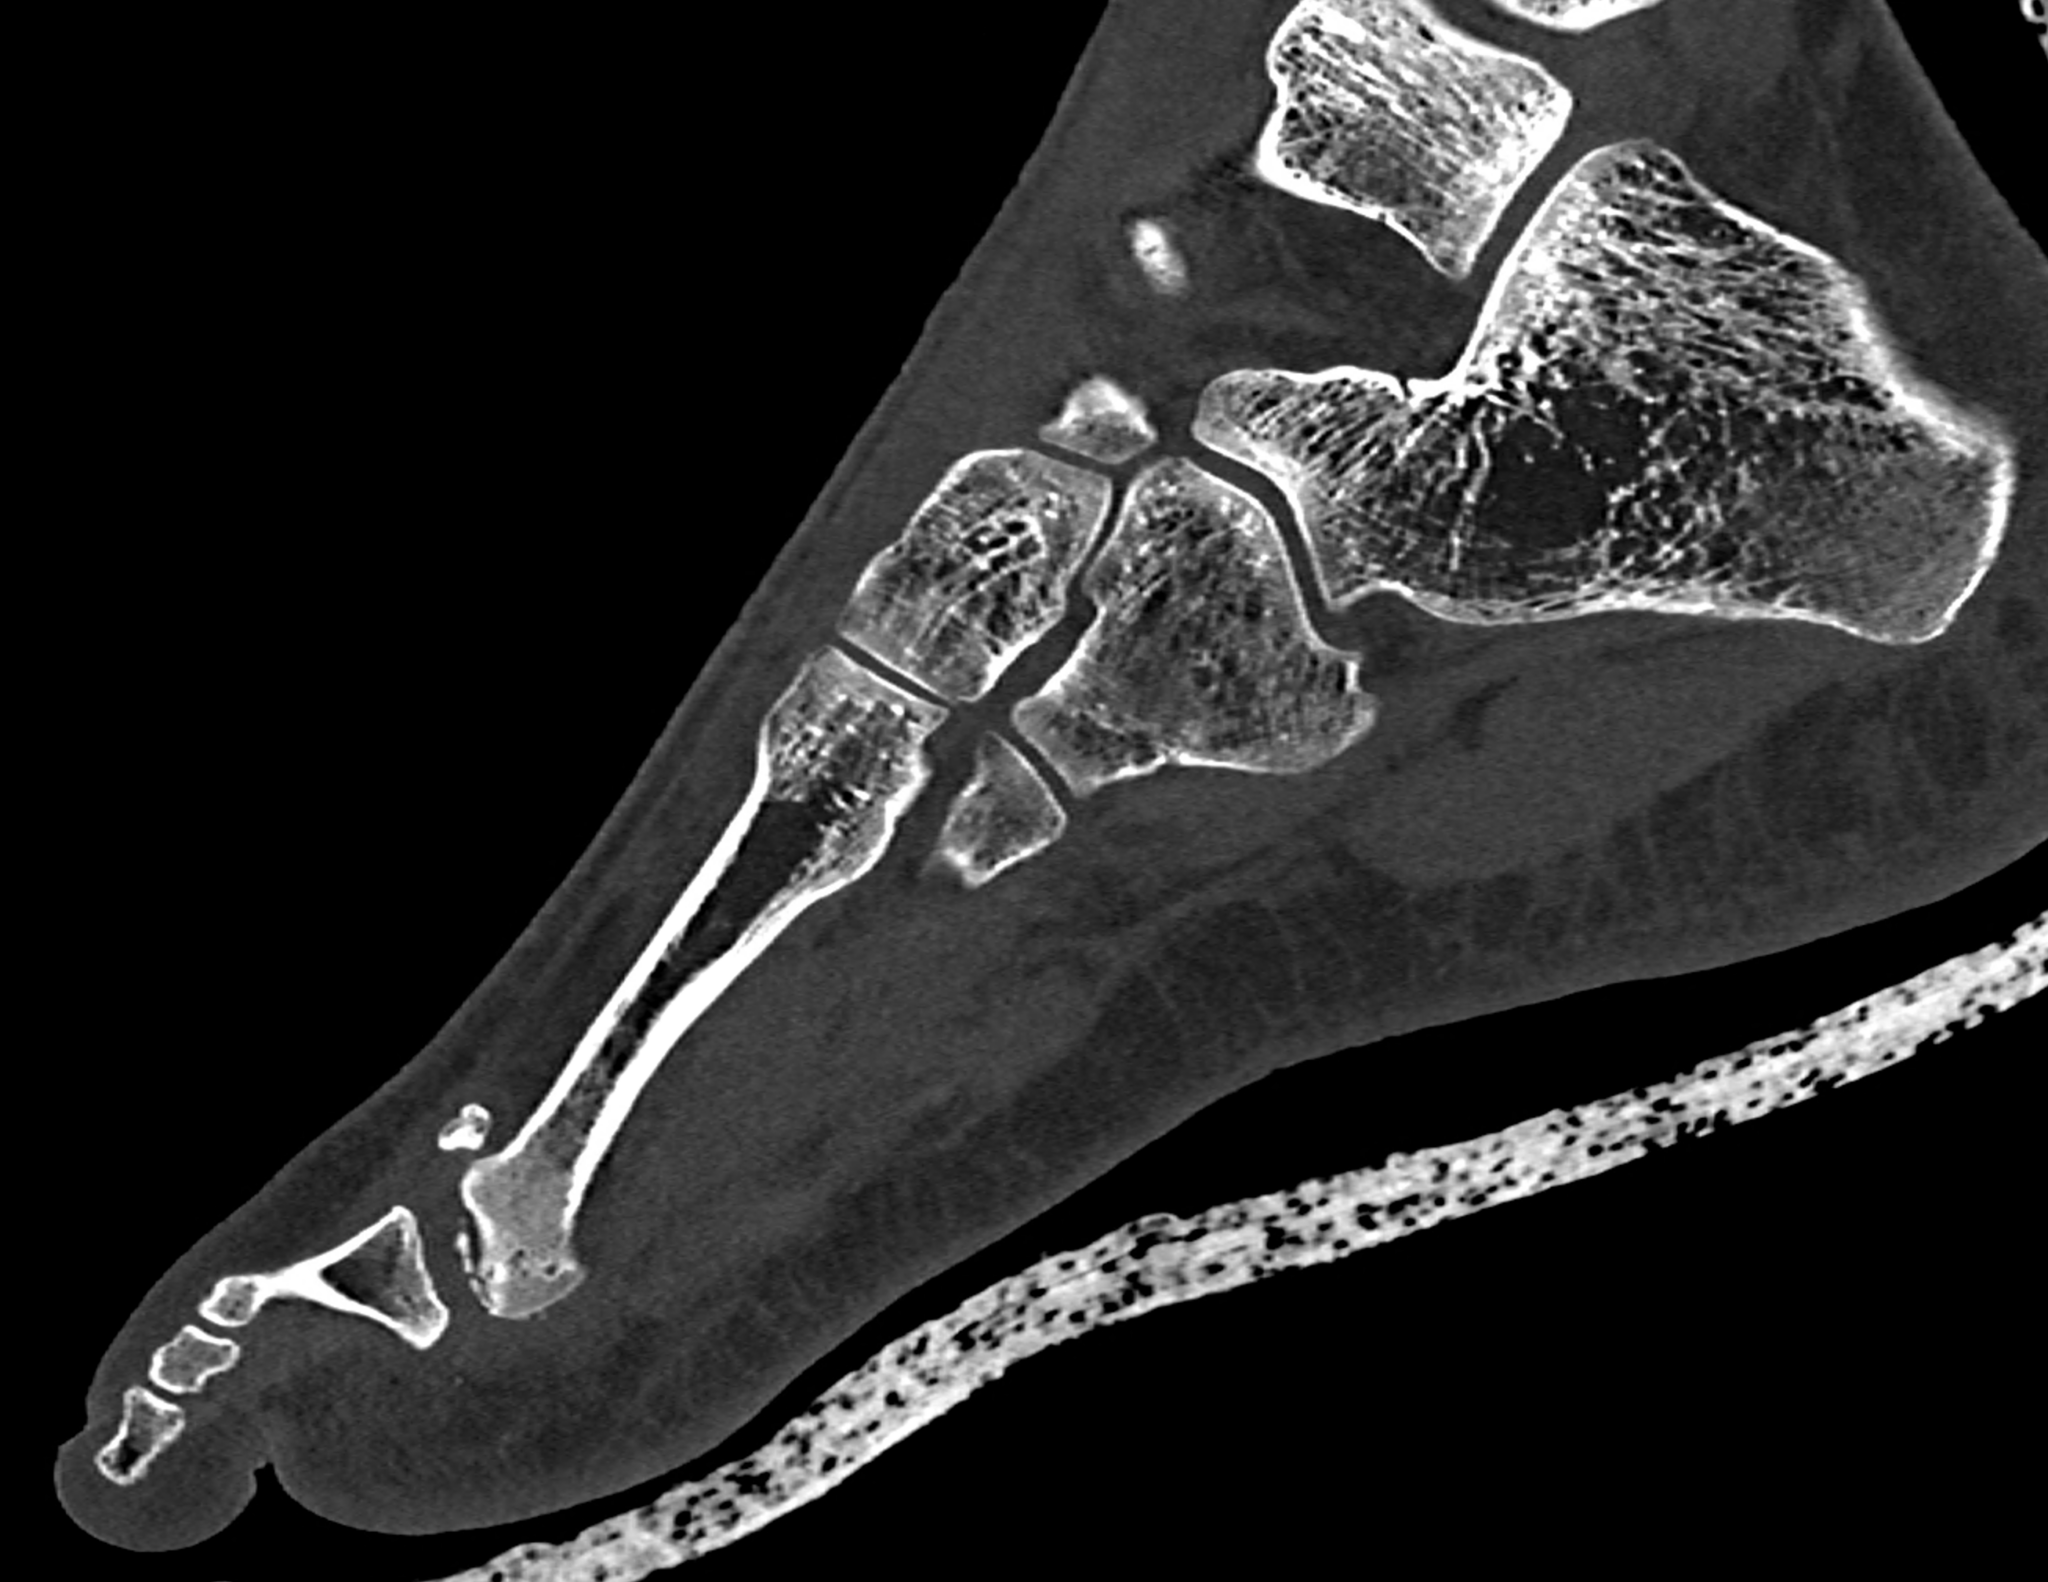

Freiberg-Koehler disease is aseptic necrosis of the head of the second or third metatarsal bone. It is more common in girls during puberty and skeletal maturation, when necrosis of the head occurs, followed by its fragmentation and subsequent deformity of the front part of the foot and the formation of pressure sores. In the acute stage, swelling and pain may occur in the area of the transverse flat arch of the foot. However, it very often progresses without any symptoms and only begins to manifest itself at a later age in connection with transverse flatfoot, with pain and pressure sores under the metatarsal heads in the front part of the foot. In the acute stage in growing children, pain in the front of the foot usually occurs after and following exertion. CT scans show fragmentation and dorsal subluxation of the distal fragments in aseptic necrosis of the metatarsal head more clearly than plain X-rays. Necrosis manifests itself in a changed structure and, in later stages, a significant change in shape; often, significant destruction of the metatarsal head can be seen.

When using ultra-high resolution CT with the smallest possible detector element, even the smallest details of bone changes can be visualized using photon-counting CT. By reconstructing images with a width of 0.2 mm and an overlap of 0.1 mm, there is a significant improvement in resolution in the planes of the reconstructed images in the metatarsal axis in the long axis of the foot, but also in the plane perpendicular to it, which better displays the metatarsophalangeal joint in the laterolateral direction.

two perpendicular multiplayer reconstruction of foot targeted to the third metatarsal head